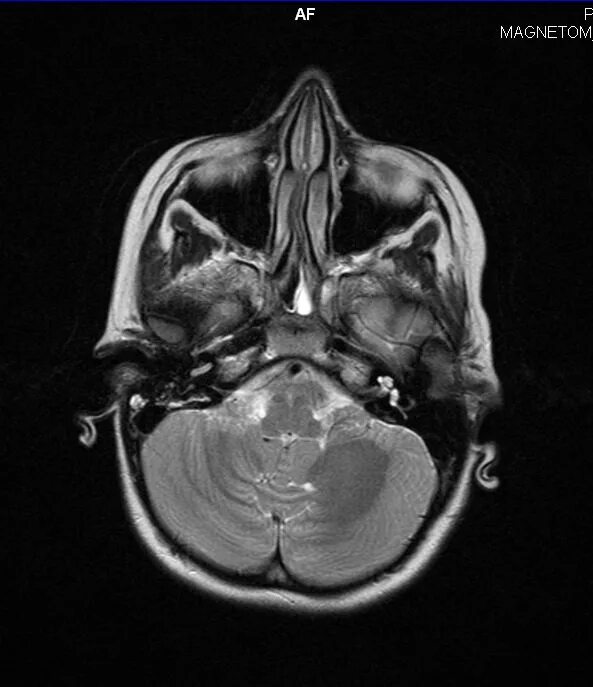

Сфеноидит симптомы у взрослых